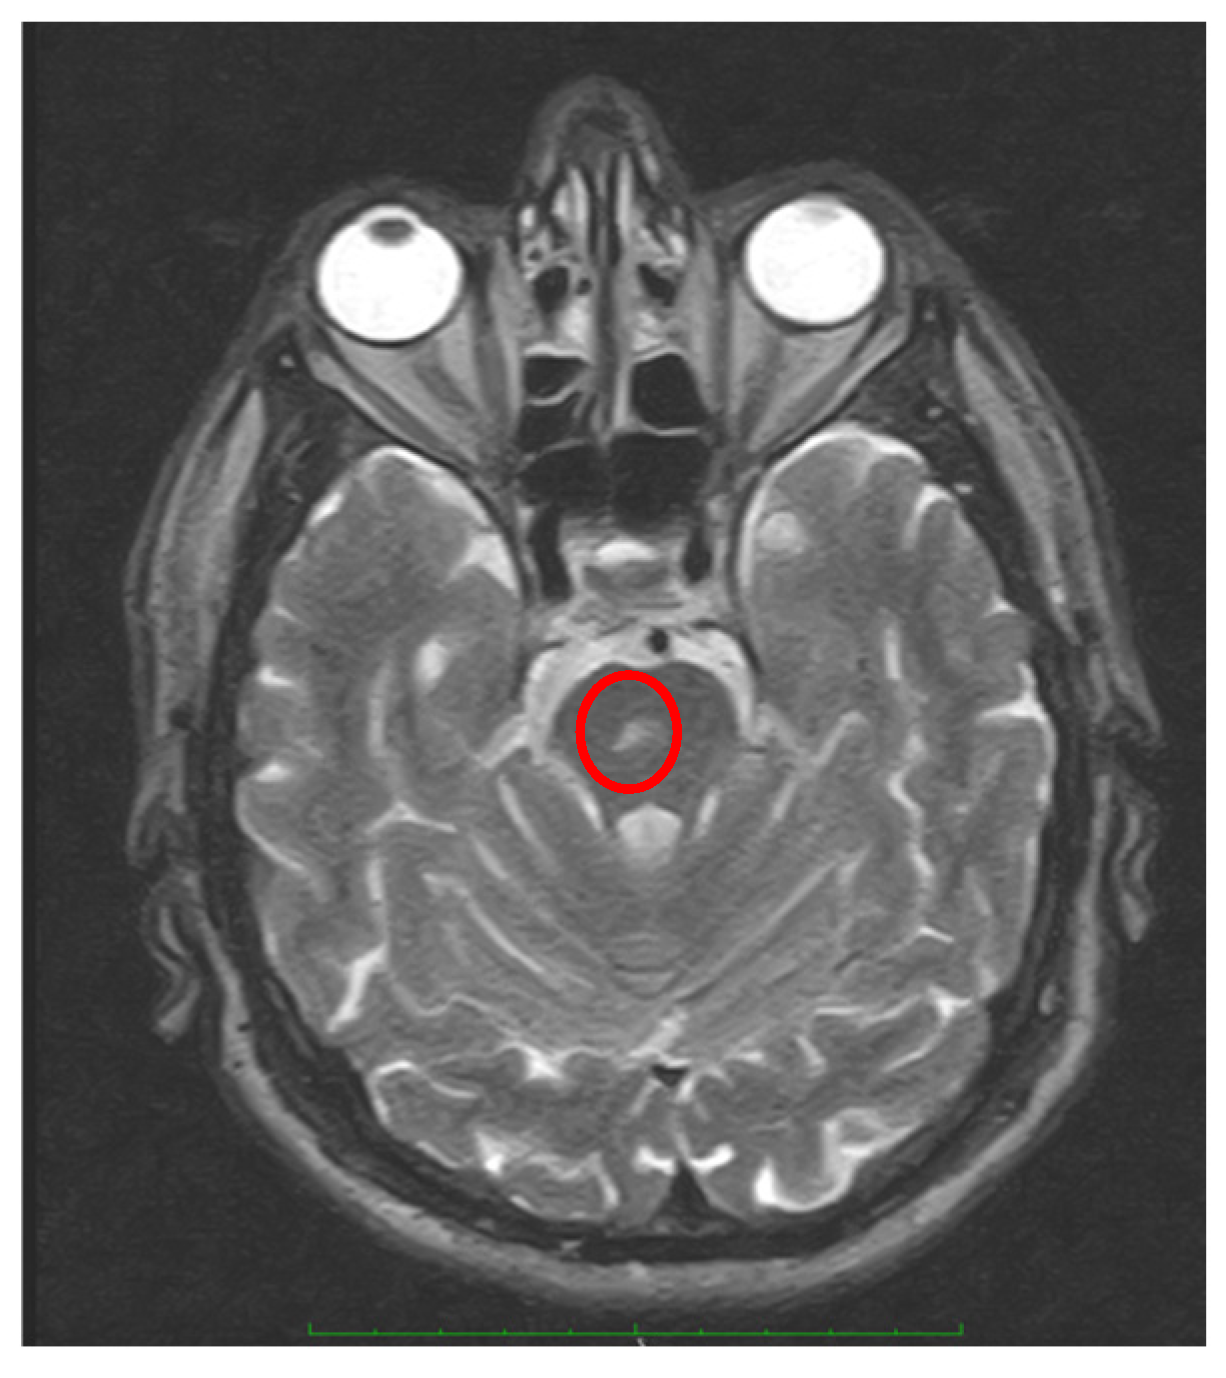

- Apogeotropic bidirectional horizontal nystagmus. More commonly associated with cerebellar disease [56,64], this type of CPN shows no latency and no associated vertigo, lasts as long as the position is maintained, and is reproduced by returning the patient to the same position. A brainstem lesion could induce an apogeotropic CPN because of damage to the connection from the nodulus and uvula (and sometimes tonsil) to the vestibular nuclei [18,58,59,60,61,62,63,64] (Figure 4).